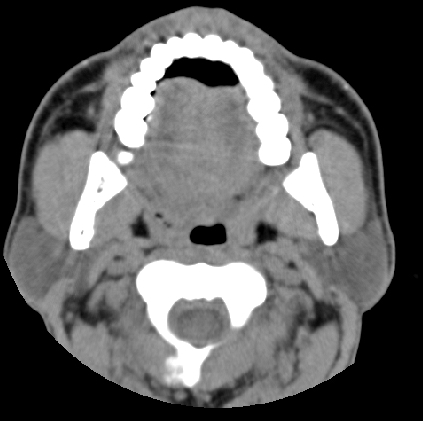

男性 49岁 劳累精神紧张后感咽部不适,疼痛,查:右上鄂肿胀

右侧扁桃腺肿大,但与周围组织分解清晰,考虑炎性

根据病史是慢性反复发作的吧的吧,病灶还比较局限,考虑慢性咽炎扁桃体炎可能性大

右侧腭扁桃体肿大,原因待查;建议行进一步检查排除肿瘤性病变可能。